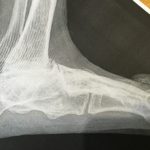

przed operacją

RTG przed operacją